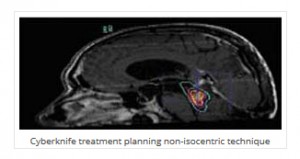

Το CyberKnife® συνδυάζοντας τα πλεονεκτήματα της μεγάλης ακρίβειας εντόπισης, εύκολης και αναίμακτης προσπέλασης και τη δυνατότητα μη ισοκεντρικής ακτινοβολίας, φαίνεται να αποτελεί τη λύση επιλογής σε πολλές περιπτώσεις γλοιωμάτων. Εφαρμόζεται επί υποτροπής του όγκου μετά από προηγηθείσα κλασσική ακτινοθεραπεία αναγκαίας για την κάλυψη των συνήθως ανωμάλου σχήματος γλοιωμάτων.